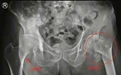

陈大爷今年88岁高龄,前不久在家中不慎摔倒,左髋部着地,由家人送至当地医院就诊,CT显示陈大爷为左股骨粗隆间粉碎性骨折,于是在当地医院住院。

▲术前双髋关节X片